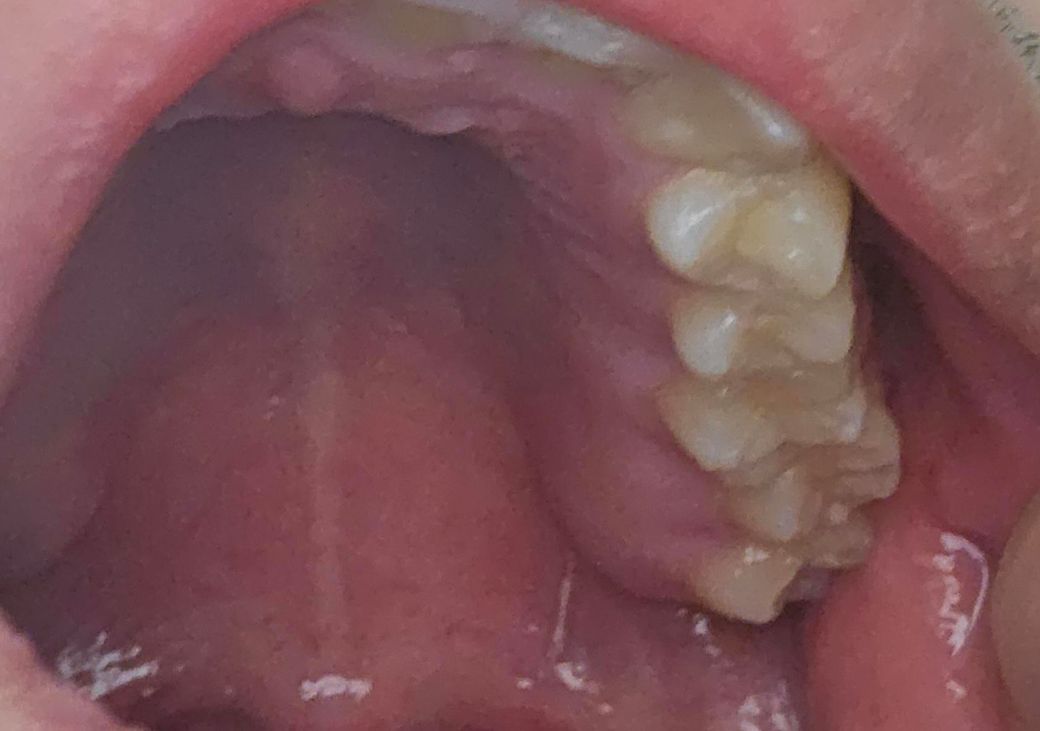

혹시 어금니가 이상하게 난게 아닌지 고민입니다

어금니가 벌어져서 나는거 같아서 고민입니다. 씹는데 문제는 없습니다. 미관적으로 좋아보이는걸 원하진 않습니다. 그냥 문제가 없는지 궁금합니다.

• 1번 째 사진